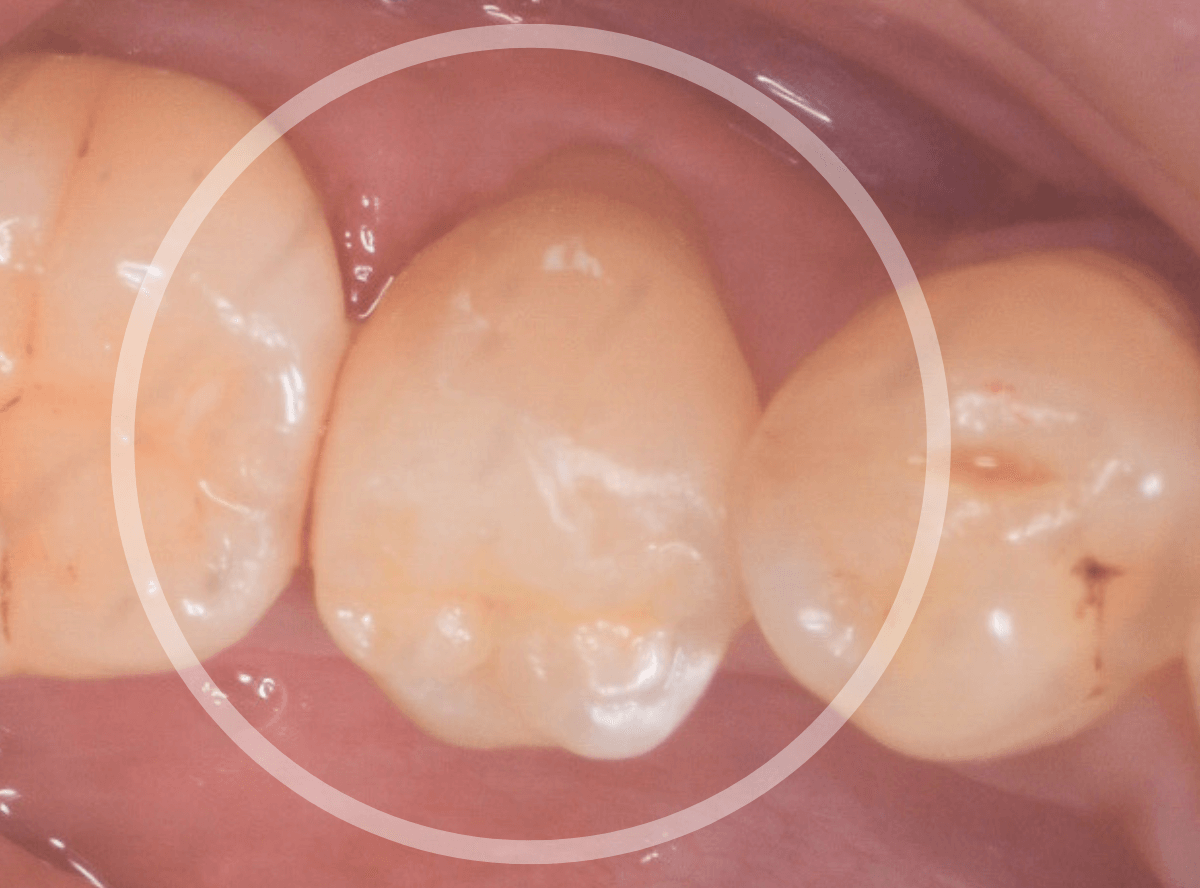

Case.30 上の奥歯のセラミック治療

メンテナンス中に、虫歯が見つかった方のケースです。

大きな虫歯でしたので、しばらく経過観察しましたが、特に症状もありませんでしたので、患者さんの希望に伴い、ジルコニア・インレーで治療をします。

治療後の状態です。

ジルコニア・インレーはE-MAX・インレーより審美性に劣るのですが、患者さんにもご満足いただける仕上がりになり、ホッとしました。

| 費用 | ジルコニア・インレー (70,000円)x2 +保険治療費用(虫歯除去など) |

(2025年2月)